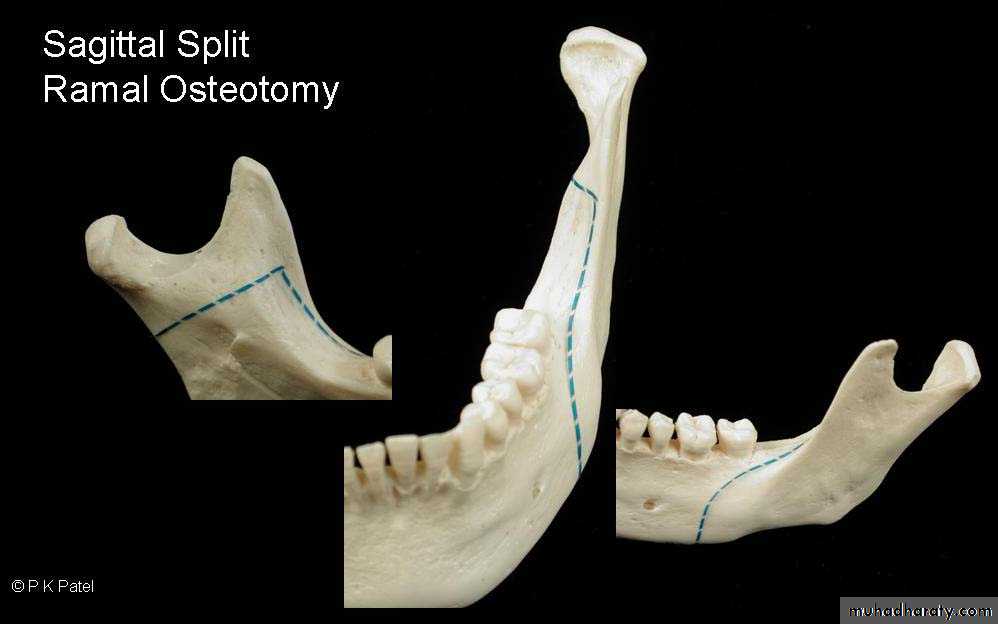

Sagittal split osteotomy

Introduced by Trauner and obwegeser, modified by Dal pont and Hunsuk.The natural plane of cleavage between the buccal and lingual cortical plates of the ramus is used to develop a sagittal splitting separating the proximal (condylar segment) from the distal (dento-alveolar segment).

Sagittal ramus osteotomy